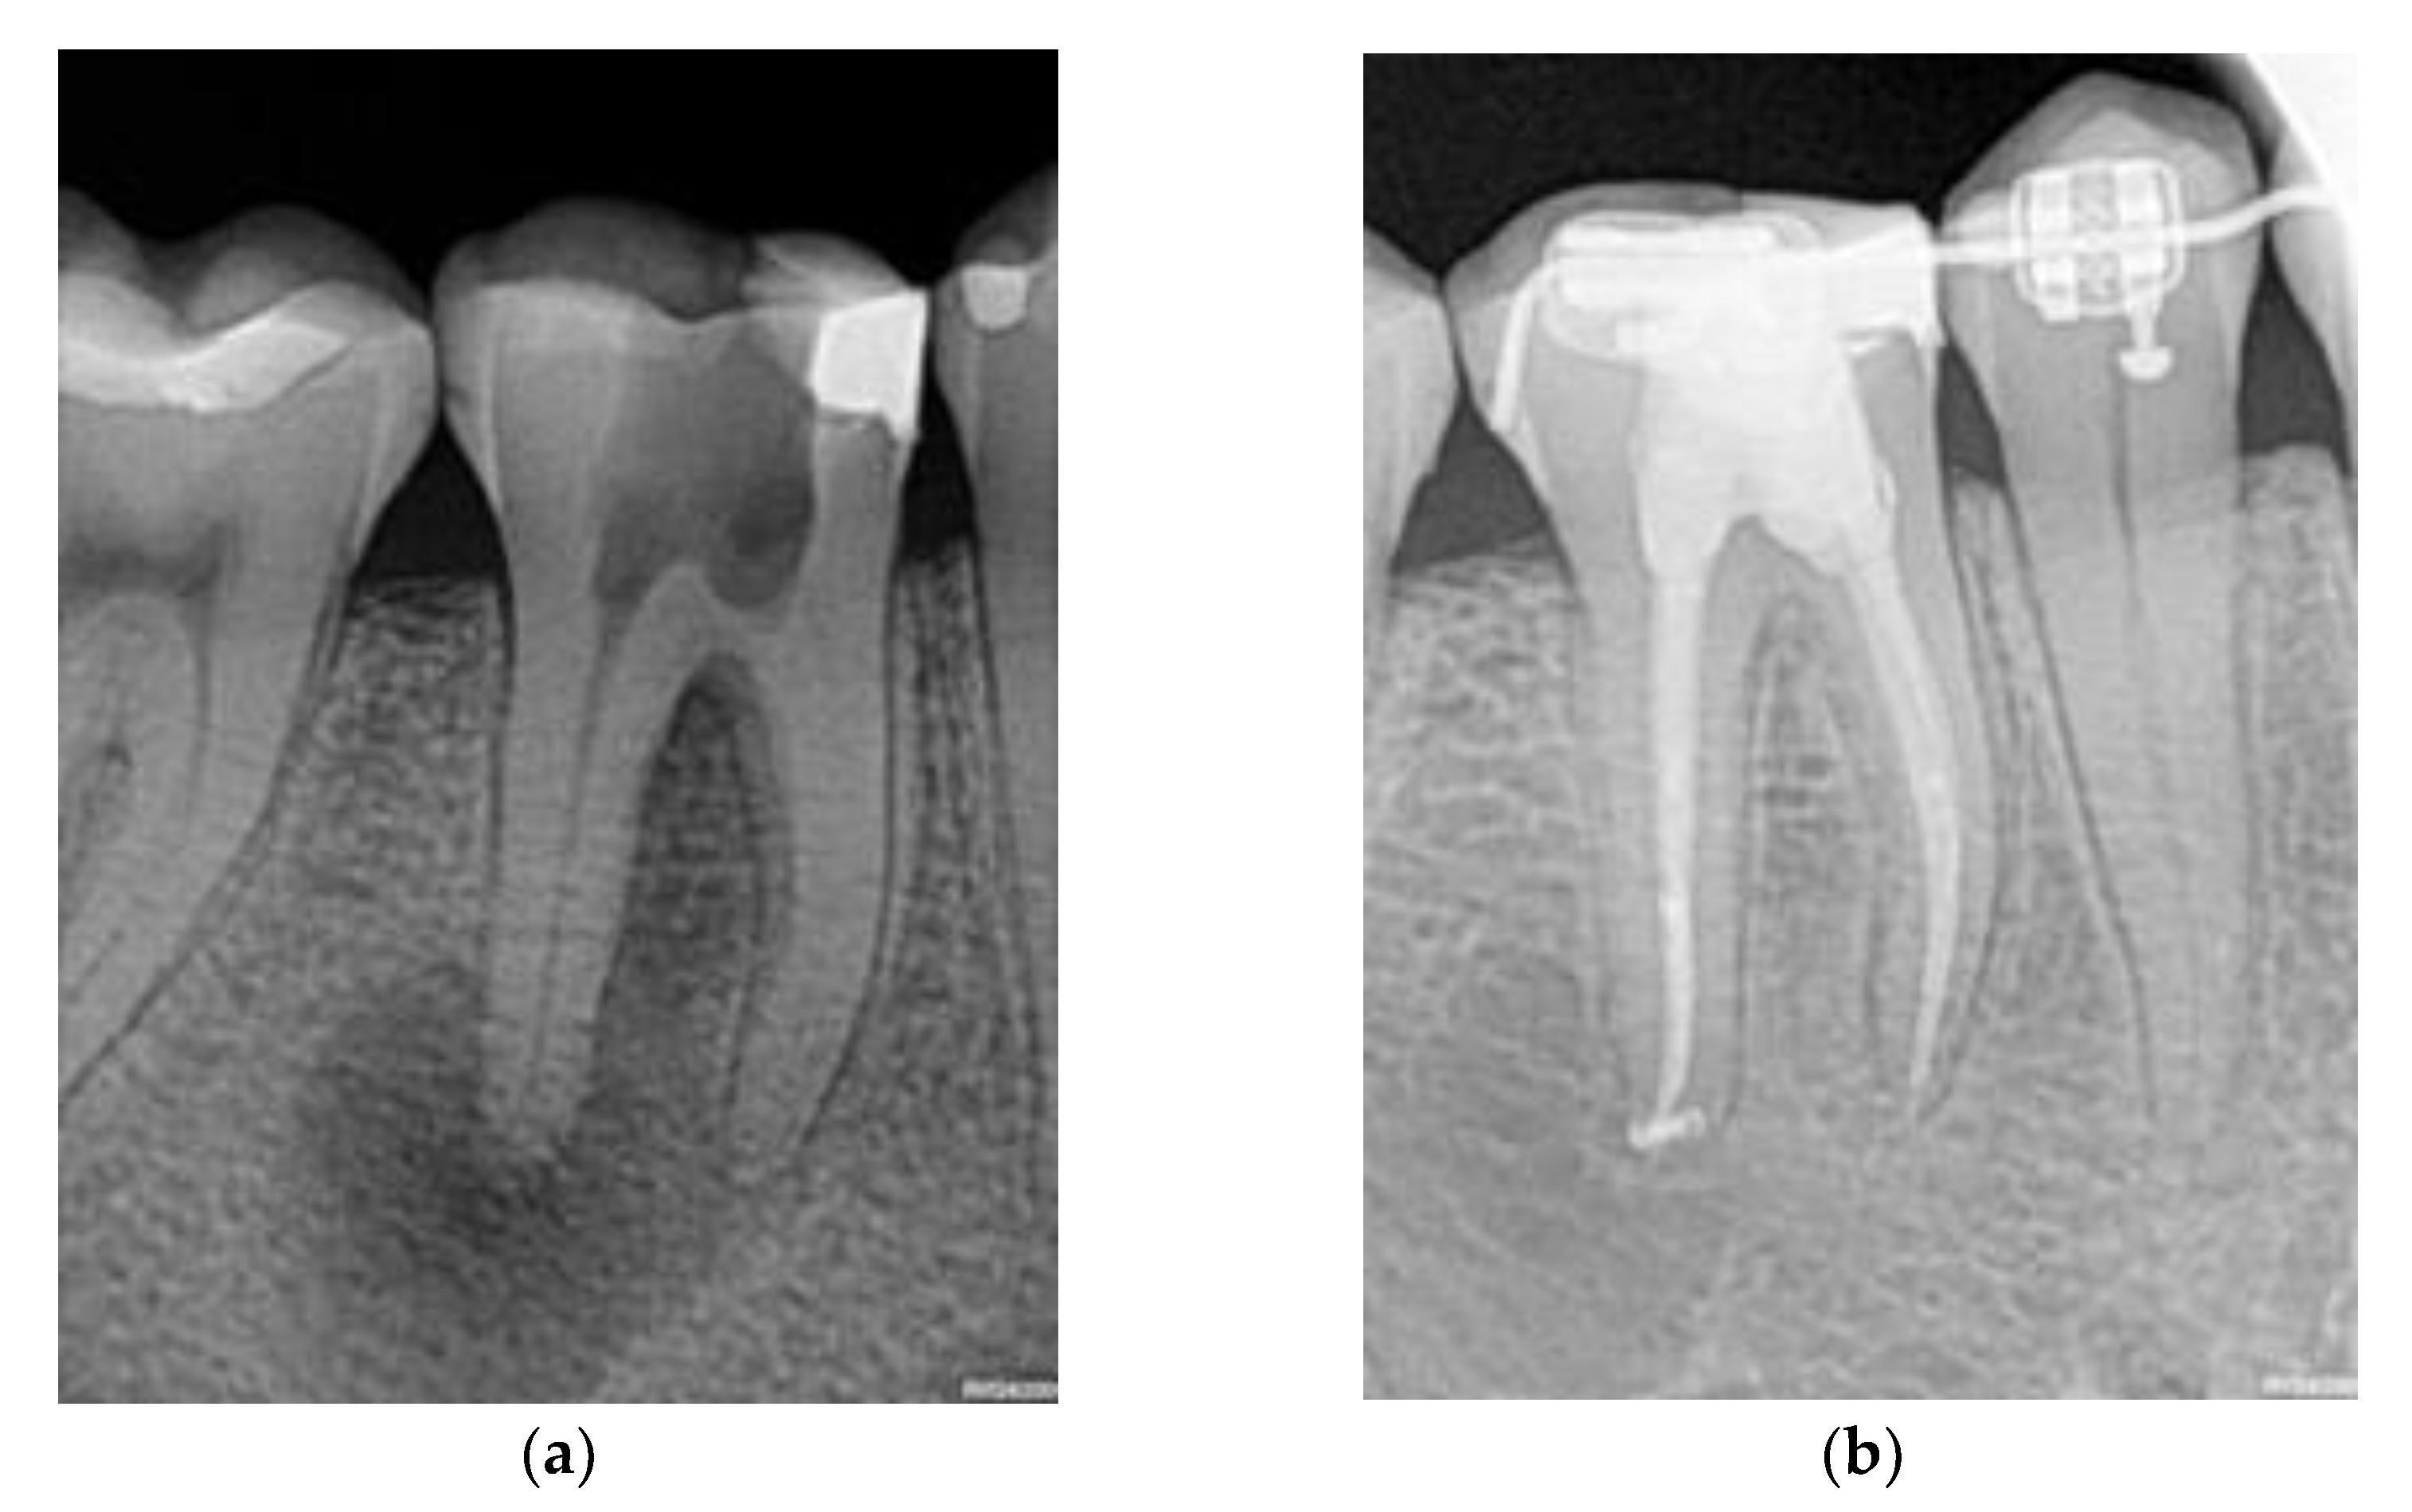

- Results of a complementary thermal test with an ice pencil and periapical radiography; and